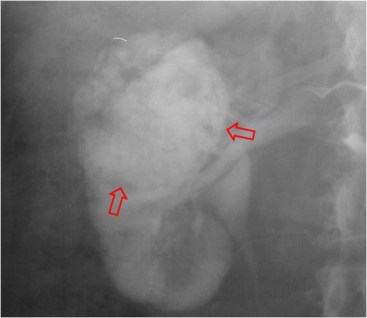

SIGNO DEL BORDE o SIGNO DEL ANILLO HIDRONEFRÓTICO

Signo de obstrucción renal en la urografía intravenosa, más frecuente en la uropatía obstructiva crónica. Consiste en el delgado anillo de parénquima renal opacificado que rodea el sistema pielocalicial dilatado, dando un aspecto de pielograma negativo.

Aunque en el caso presentado, el estudio no es una urografía sino una arteriografía, el signo es similar. Vemos una delgada capa de parénquima (flecha) que rodea a los cálices dilatados, en esta fase aún no opacificados.

No debe confundirse este signo con el Signo del borde, aunque tienen semejanzas. En los dos se produce un adelgazamiento de la cortical renal: en el signo del borde está causado por hidronefrosis; en el signo del borde fino se origina por la presencia de una o más masas renales. Tampoco hay que confundirlo con el Signo de los anillos de Dunbar, aunque ambos se ven en la hidronefrosis. El anillo hidronefrótico es el realce cortical mientras que los anillos de Dunbar corresponden al contraste en los túbulos renales.

Fase vascular precoz del mismo estudio en el que puede verse el arqueamiento de las ramas arteriales como consecuencia de la hidronefrosis.